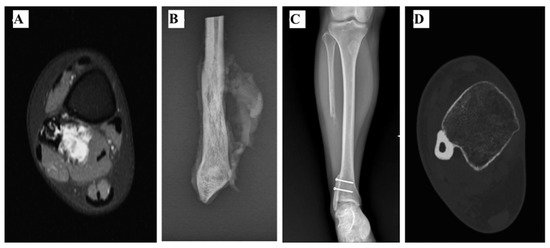

2.2. Rotational Vascularized Fibula Transposition

| 4 | 120 | 9.5 | Yes | Yes (periosteal) | No | No | 2 | PedR VFT | 20 | Peroneal nerve palsy Chronic pain | No | 30 |